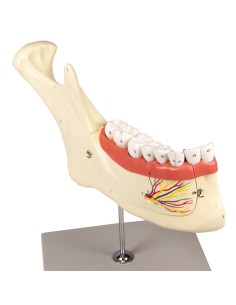

Erler Zimmer, modello anatomico per spiegare la corretta igiene orale D217

Erler Zimmer, modello anatomico di serie di morfologia dentale, ingrandito di 10 volte...

Erler Zimmer, modello anatomico di metà mandibola superiore e inferiore, ingrandita...

Erler Zimmer, modello anatomico per spiegare la corretta igiene orale D216

Erler Zimmer, modello anatomico di dente cariato, ingrandito di 10 volte D214